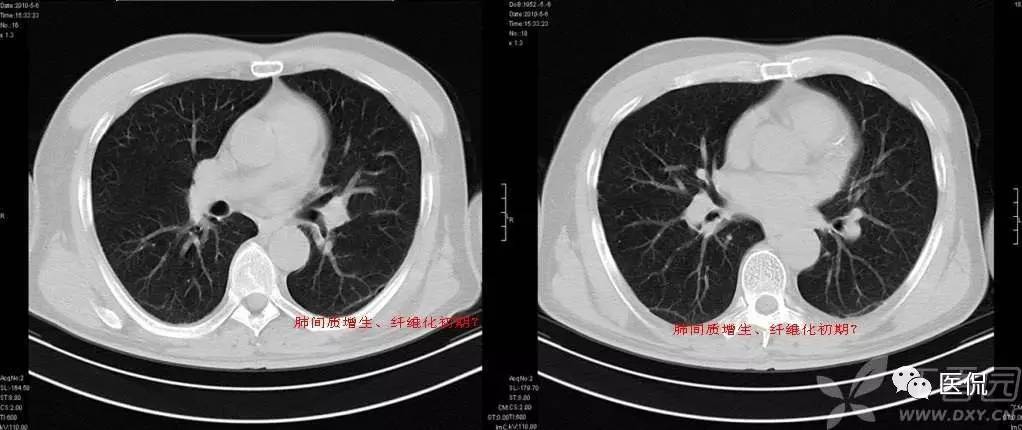

胸膜下弧线(SCLC)

肺胸膜下弧线影像(SCLS)的病理基础

国外学者对此征象的CT与病理对照研究指出,SCLS是细支气管周围纤维性增厚及肺纤维化引起的肺泡变扁和肺不张。构成SCLS的肺不张为肺脏皮质与髓质交界处的盘状肺不张,肺不张的发生与肺间质纤维化后肺脏的顺应性减低有关。指出肺脏蜂窝状改变的边缘融合也可形成SCLS,SCLS位于蜂窝之间,这在HRCT图像上可清楚地显示。临床发现,SCLS发生在慢性肺炎之后,少数发生在慢性支气管炎合并肺间质纤维化患者吸气不足状态,深吸气时大部分消失,也有发生在阻塞性肺不张后,这些表明SCLS为肺脏局部通气不良发生的盘状肺不张。胸膜广泛钙化,SCLS与胸膜钙化的范围一致,肺内也有轻度的肺间质纤维化改变,胸膜钙化可能使胸膜下肺组织的顺应性下降,从而对SCLS的形成有促进作用。胸膜增厚与胸膜结节也可能引起类似的结果。

SCLS的HRCT形态特点

SCLS与生理性的肺下垂部线性影像不同,生理性胸膜下线位于肺脏的最低部,在仰卧位时位于下叶后部,而转变为俯卧位时下叶后部的线性影像消失,生理性胸膜下线多距胸膜下5mm以内,可合并局限性肺脏密度增高。而SCLS虽然在肺脏后部多见,但多超过一个肺段的范围,并可位于肺脏非下垂的部位。体位变换时其形态无变化,也不会消失。多数SCLS表面光滑、呈连续状,少数为不规则及不连续状。煤工尘肺的SCLS可有结节状影,或厚度较大。

SCLS的诊断意义

SCLS可见于多种肺间质纤维化的疾病,如慢性支气管炎合并肺间质纤维化,煤工尘肺,特发性肺间质纤维化,胶原病引起的肺间质纤维化,及结节病引起的肺改变等。慢性支气管炎,特发性肺间质纤维化,煤工尘肺及胶原病引起的肺脏改变等均可出现,占90.3%。以往一些作者曾认为SCLS在石棉肺多见,或认为此征象是石棉肺病人的特有表现。但临床研究的结果表明,SCLS是肺间质纤维化的一种常见征象,见于多种疾病。此外,SCLS还见于炎症、肺瘀血和吸气不足状态。对于肺间质纤维化的病例,SCLS为肺间质纤维化的早期改变。

SCLS周围无肺间质纤维化征象者占25.71%,仅有小叶内间质增厚及小叶间隔增厚者占28.57%,发生较多蜂窝改变的仅占20%。SCLS的长度与肺间质纤维化的严重程度有关,有人对随访的肺间质纤维化逐渐加重的患者,发现SCLS也由短线型发展为长线型。即使SCLS可发生在有蜂窝的部位,但蜂窝改变多较轻微,而在蜂窝改变较密集之处未能见到SCLS。有研究指出,SCLS开始发生在肺间质纤维化轻微的部位,5年后该部位发生严重蜂窝改变,SCLS则不能显示。这表明SCLS的发生、延长与肺间质纤维化加重有关,但出现严重蜂窝后SCLS则不能显示。

总之,SCLS可以变小或消失,表明SCLS有些为可逆的改变。不同的疾病SCLS在形态上多无显著的差异。煤工尘肺SCLS可有细小结节,此结节与肺内结节的形态相似,代表了煤工尘肺的形态特点。但对大多数疾病而言,SCLS缺乏鉴别诊断价值。